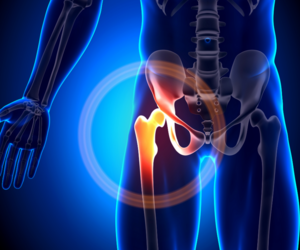

Comprehensive Joint Replacement Surgery

Expertise in total hip replacement, partial knee replacement, and complex revision surgeries means you’re in capable hands for every stage of your joint care journey.